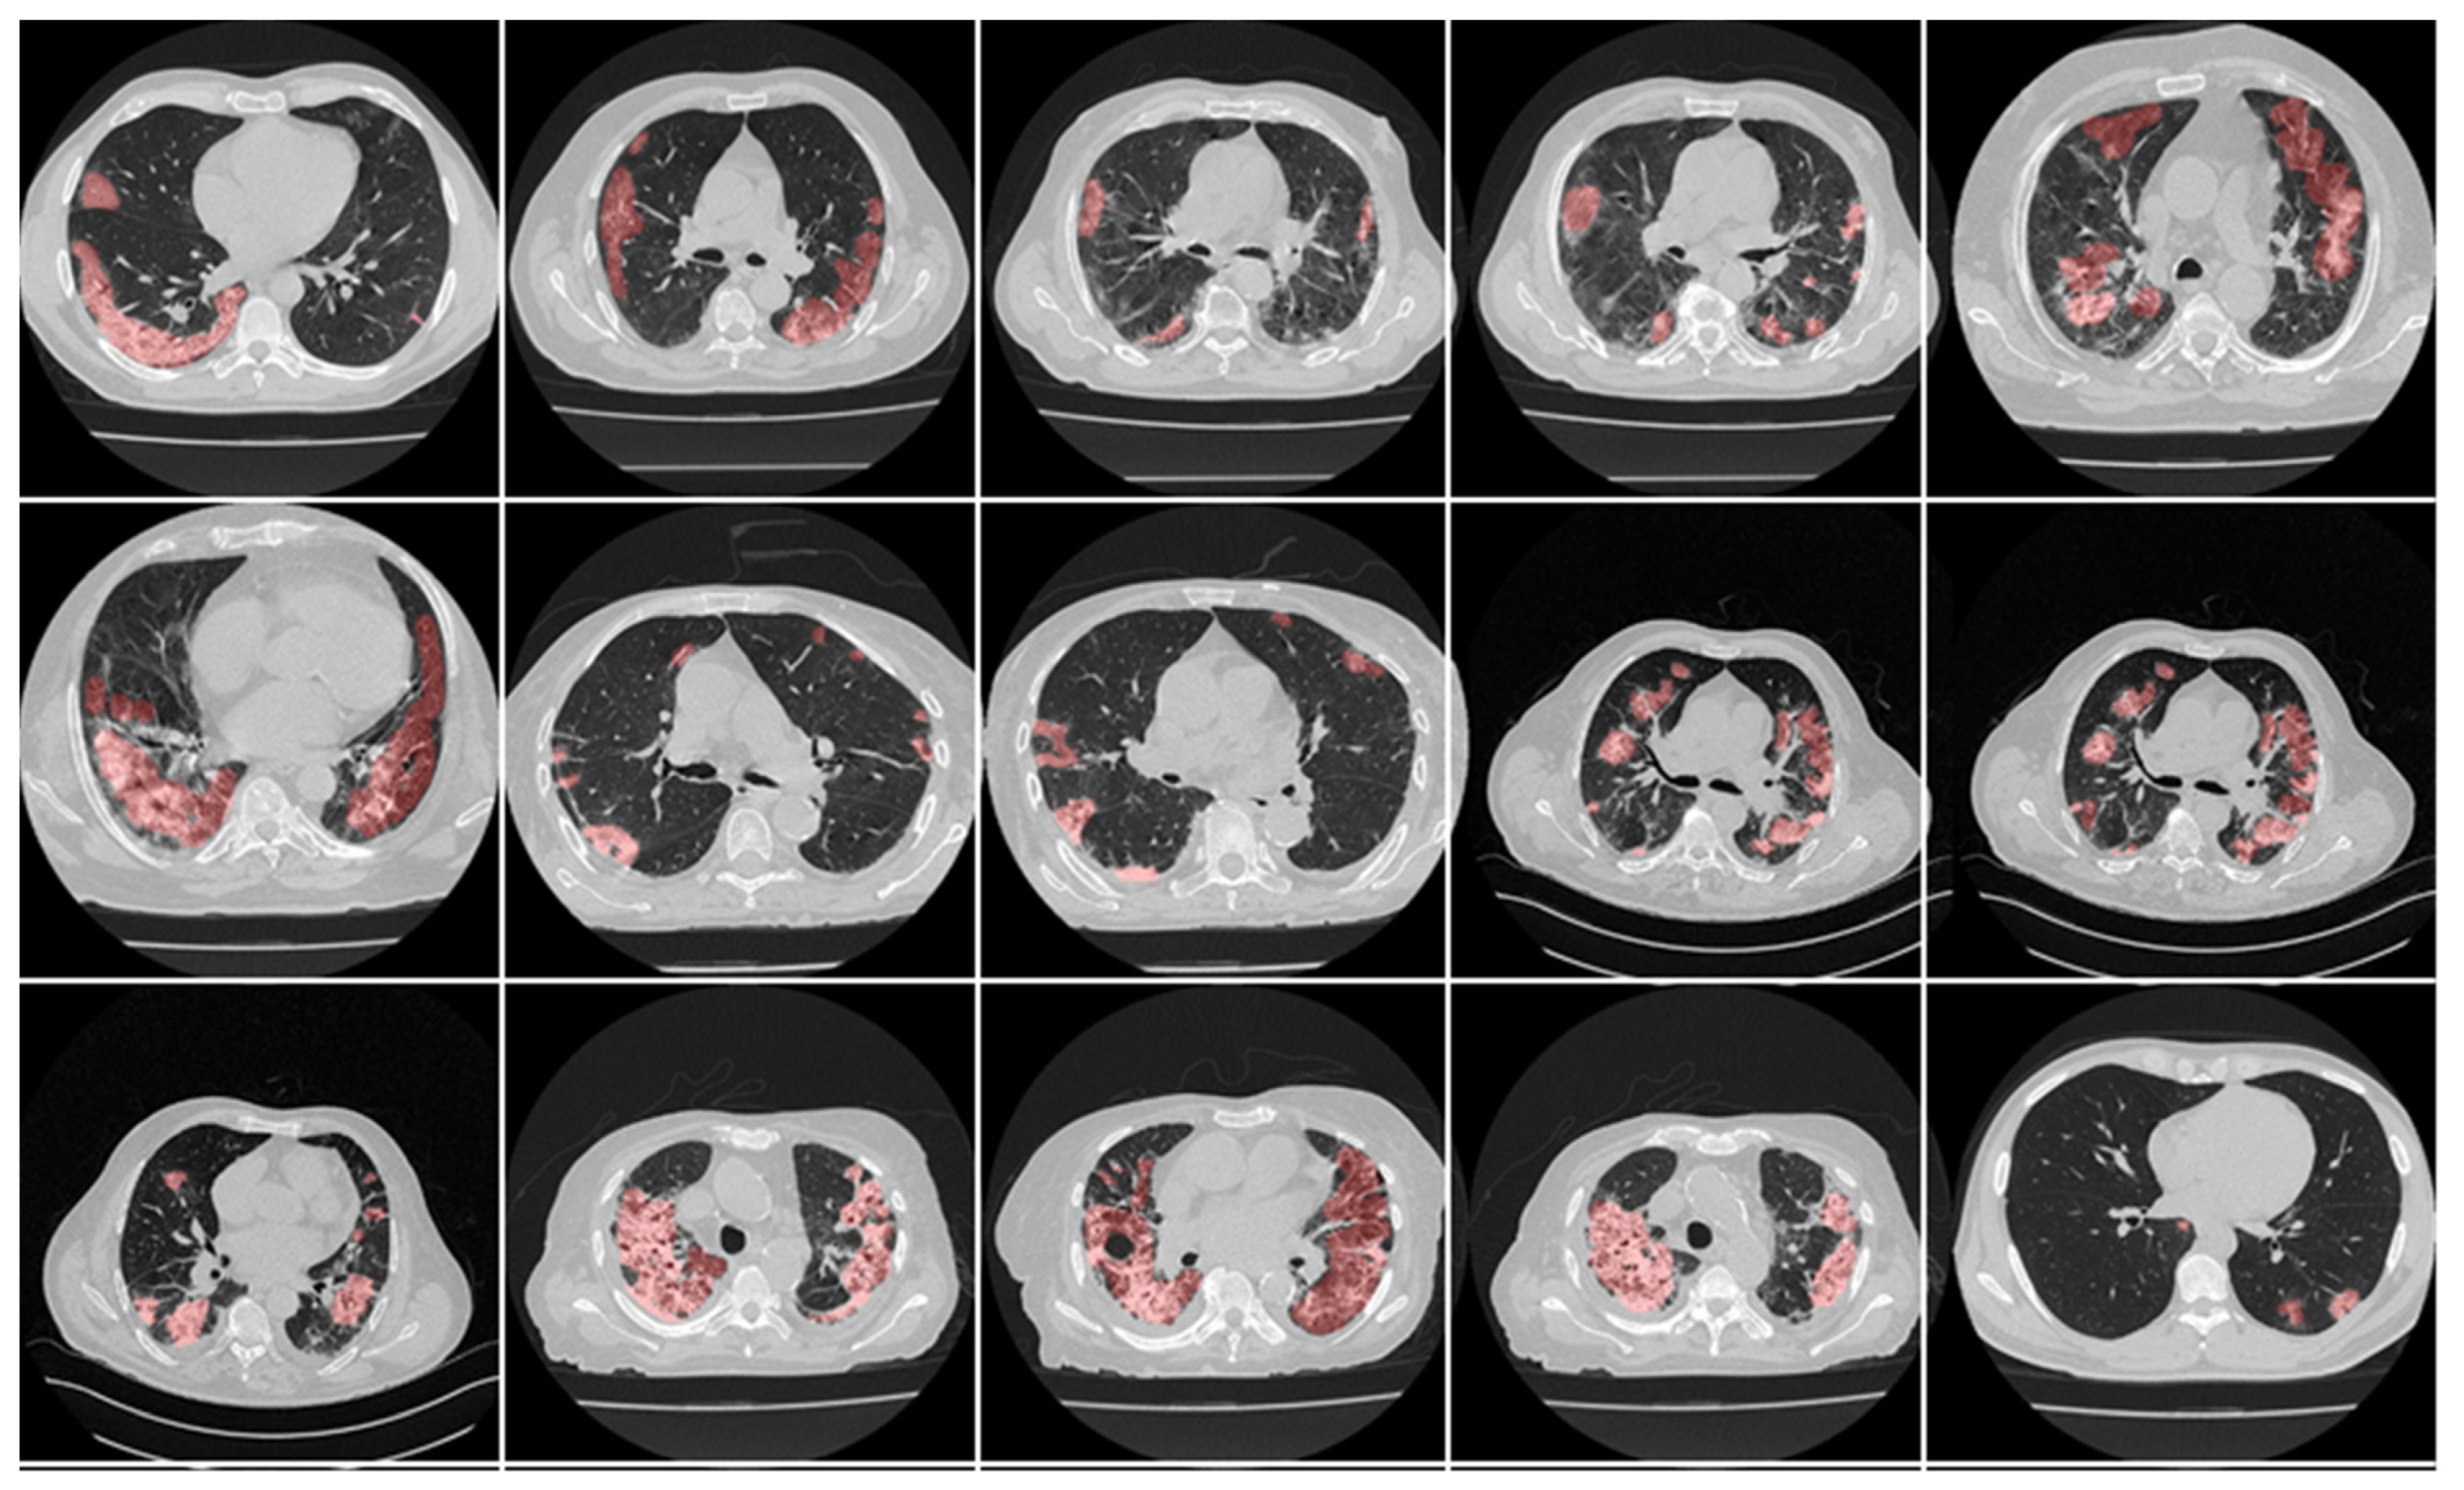

3.1. Results

3.2. Performance Evaluation